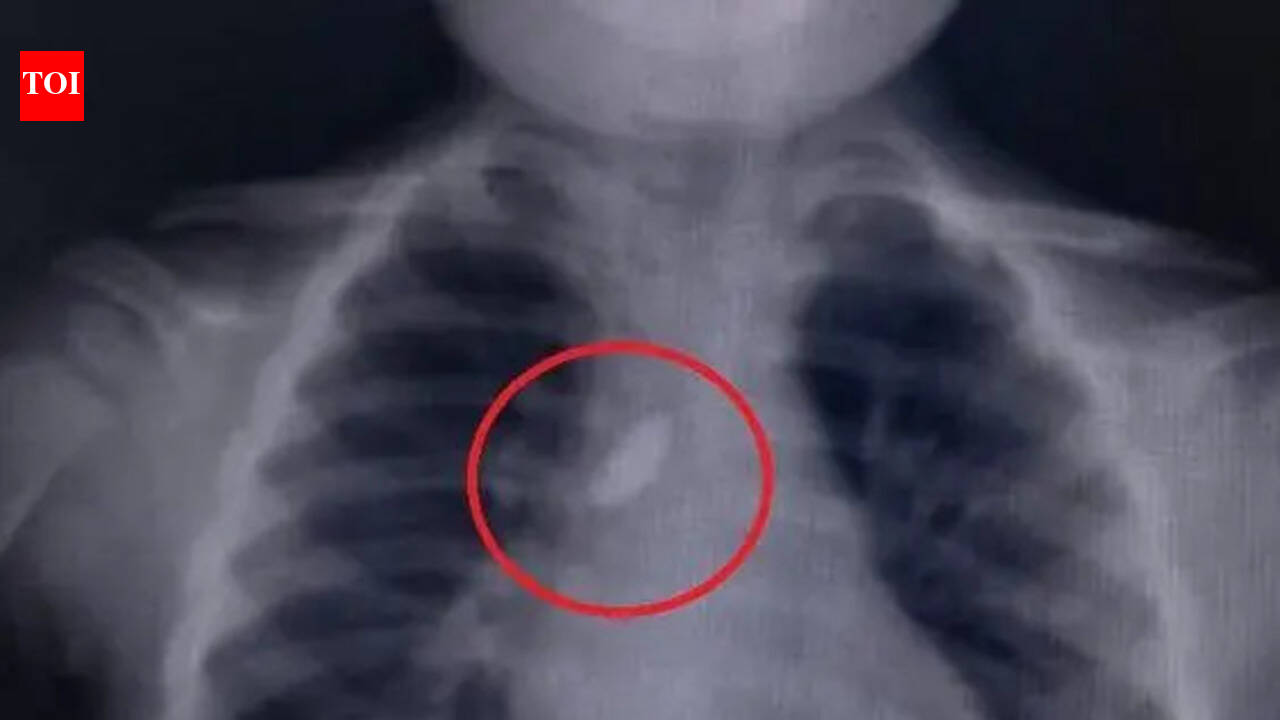

पुणे : शहरातील ससून सामान्य रुग्णालयातील कान, नाक आणि घसा (ईएनटी) विभागातील श्वासनलिकेतील दगड डॉक्टरांनी यशस्वीरीत्या काढल्याने नुकतेच एका वर्षाच्या चिमुरड्याचा जीव वाचला.हॉस्पिटलच्या सूत्रांनी TOI